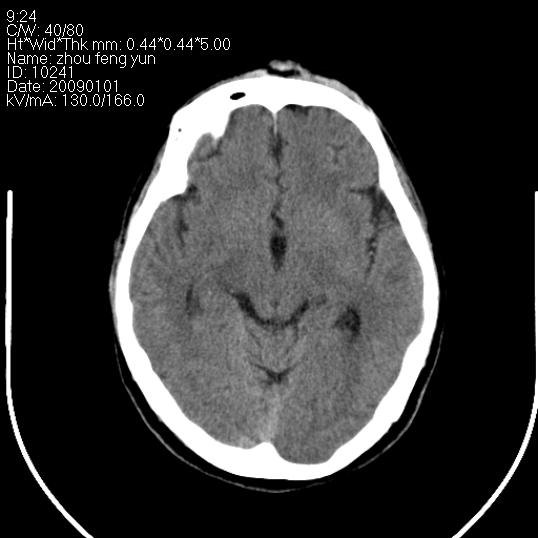

以下是引用hhcckk在2009-1-1 16:39:00的发言:[br]胼胝体嘴、膝部及部分体部发育不全,为囊状影替代,两侧侧脑室分离,脑室后角扩张[br][br]诊断:胼胝体发育不良[br][br]胼胝体发育不良(dysgenesis of the corpus callosum)是最常见的颅脑畸形,是胚胎期背部中线结构发育不良的一种形式。主要包括胼胝体缺如和部分缺如。胼胝体发育不良还可合并其他畸形,如胼胝体脂肪瘤、蛛网膜囊肿、脑膨出、chiari畸形、灰质异位症、脑回畸形等。[br][br]ct诊断要点:[br]1. ct横断扫描可见两侧侧脑室明显分离,脑室后角扩张,形成典型的蝙蝠翼状侧脑室外形。[br]2. 第三脑室扩大并向上插入两侧脑室体部之间,严重者第三脑室可上移到两侧大脑半球纵裂的顶部。在ct冠状扫描位显示更清。[br]4. 胼胝体畸形常伴有脂肪瘤,可测到其特征性脂肪密度。部分脂肪瘤的边缘可出现线样钙化[br]